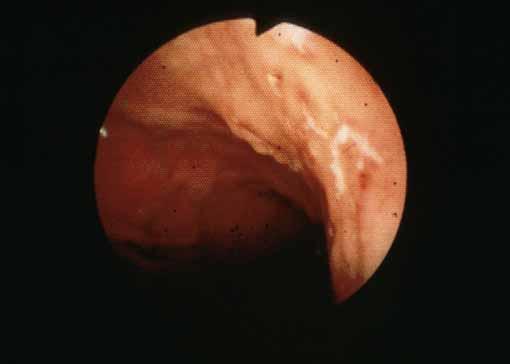

A case of Crohn's disease wih minute ulcerative lesions in the larynx, esophagus, stomach and duodenum.

[ Image ID:2518 ]

Inflammatory or ulcerative disease / lesions/Crohn disease

Location

Stomach/Body

Technique, Method

Endoscopy

Size